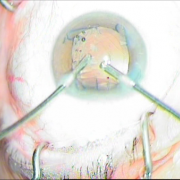

Οι σύγχρονες μικροχειρουργικές τεχνικές αποβλέπουν στον ελάχιστο τραυματισμό του οφθαλμού και στην τοποθέτηση του τεχνητού ενδοφακού στην φυσική του θέση που είναι ο οπίσθιος θάλαμος. Οι ασθενείς απολαμβάνουν τα πλεονεκτήματα των επεμβάσεων μικρής τομής χωρίς ράμματα, με άμεση αποκατάσταση της όρασης και χωρίς μετεγχειρητικό αστιγματισμό.

καταρράκτης με τραυματική

ρήξη οπ.περιφάκιου από

έγγχυση ANTIVGEF παράγοντα

του οπ. περιφάκιου